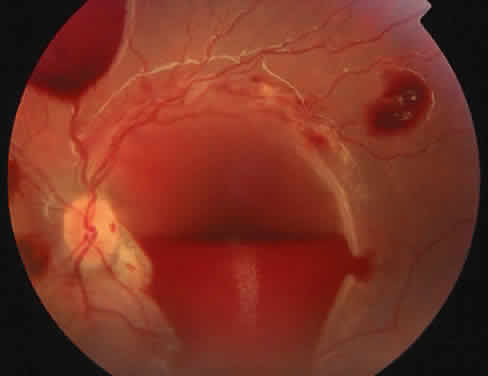

The ocular manifestations of antiphospholipid antibodies include retinal venous and arterial occlusions, amaurosis fugax, diplopia, and visual field loss.34,35 Extensive vasoocclusion, neovascularization, and vitreous hemorrhage may occur (Fig. 3). Treatment consists of photocoagulation for the neovascularization and systemic anticoagulation and immunosuppression. Vitrectomy may be required for vitreous hemorrhage. The role of systemic treatment of lupus anticoagulant in the management of ocular disease is unclear. Some investigators suggest that systemic anticoagulation be started promptly.36 The optimal duration of anticoagulation and whether antiplatelet therapy should be used are not known however. The optimal use of corticosteroids or other immunosuppressive drugs such as cyclophosphamide and azathioprine also is unknown. Two reports have found an association with the antiphospholipid syndrome and some additional retinal conditions. One report also has associated the primary antiphospholipid syndrome with central serous chorioretinopathy.37 In addition, lupus anticoagulant positivity could represent an additional risk factor for diabetic retinopathy according to a recent report.38

Fig. 3. Retinopathy associated with lupus anticoagulant with disc neovascularization and vitreous hemorrhage. (Kleiner RC, Najarian LV, Schatten S et al: Vaso-occlusive retinopathy associated with antiphospholipid antibodies [lupus anticoagulant retinopathy]. Ophthalmology 96:898, 1989.)